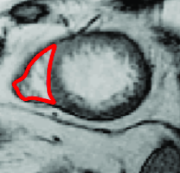

where is the mask of an ellipse parametrized by . As minimizing such a term is not straightforward, the authors optimize the energy functional iteratively, i.e. by finding the best for a fixed and then optimizing for a fixed . For complex shapes that are hard to parametrize, an alternative approach is to fit a shape template to the current segmentation as proposed in (Freedman and Zhang, 2005). Veksler (2008) proposed to incorporate a more general class of shapes, known as star shapes, into graph-based segmentation. In Veksler’s work, it is assumed that the center point () of the object is given. According to their definition, “an object has a star shape if for any point inside the object, all points on the straight line between the center and also lie inside the object” (Figure 13). The following pairwise term was introduced to impose the star shape prior:

| (33) |

This prior is particularly useful for segmentation of convex objects, e.g. optic cum and disc segmentation (Bai et al., 2014).